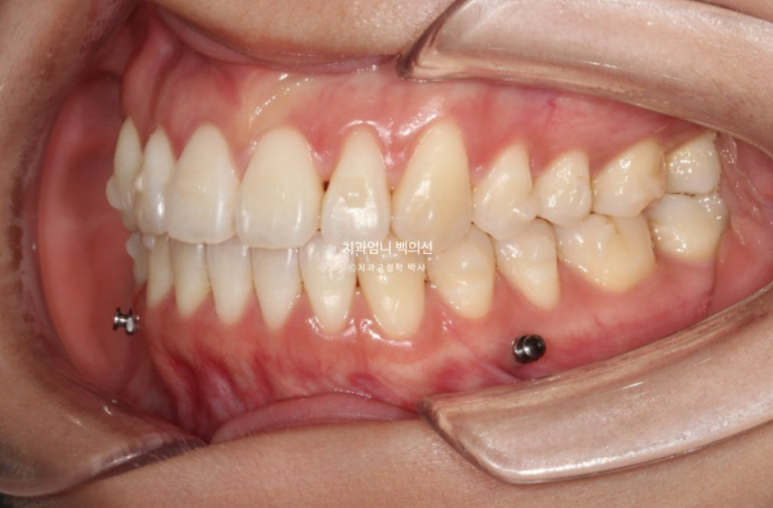

23년 11월 개방교합 치료를 위해 내원한 환자분입니다.

앞니 돌출감도 느끼는 상태입니다.

삐뚤한 치아 배열은 사랑니 공간을 이용해서 어금니를 뒤로 밀어내어 해결하기로 하고 앞니 개방교합은 어금니 함입을 통해 해결하기로 합니다.

어금니 함입은 입천장에 교정용 나사 미니스크류를 심어 도모하기로 합니다.

사랑니 공간으로의 후방이동 역시 미니스크류가 필요하죠.